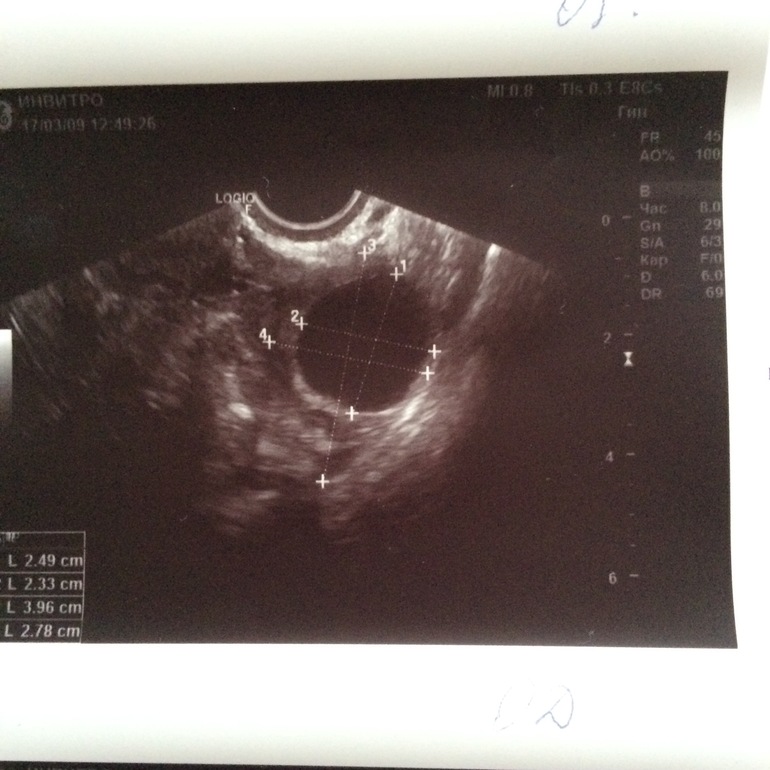

Два критерия, которые позволяют определить зрелость фолликула и надвигающуюся овуляцию при ультразвуковом исследовании: размер доминирующего фолликула должен быть от 20 до 25 мм;

Когда наступает долгожданная овуляция, размер фолликула в диаметре - 20-25 мм . При нормальном развитии в это время происходит разрыв фолликула и выход женской клетки . Но иногда разрыв не наступает, несмотря на то, что оболочка имеет максимальный размер, и ее диаметр может . . .

Размер фолликула перед овуляцией составляет в среднем 24 мм . Овуляторная фаза приходится на 12-14 день менструального цикла .

Гинеколог назначает укол для успешного выхода яйцеклетки при достижении размера фолликула - 16 - 21 мм . В каждом отдельном случае врач индивидуально определяет готовность к овуляции .